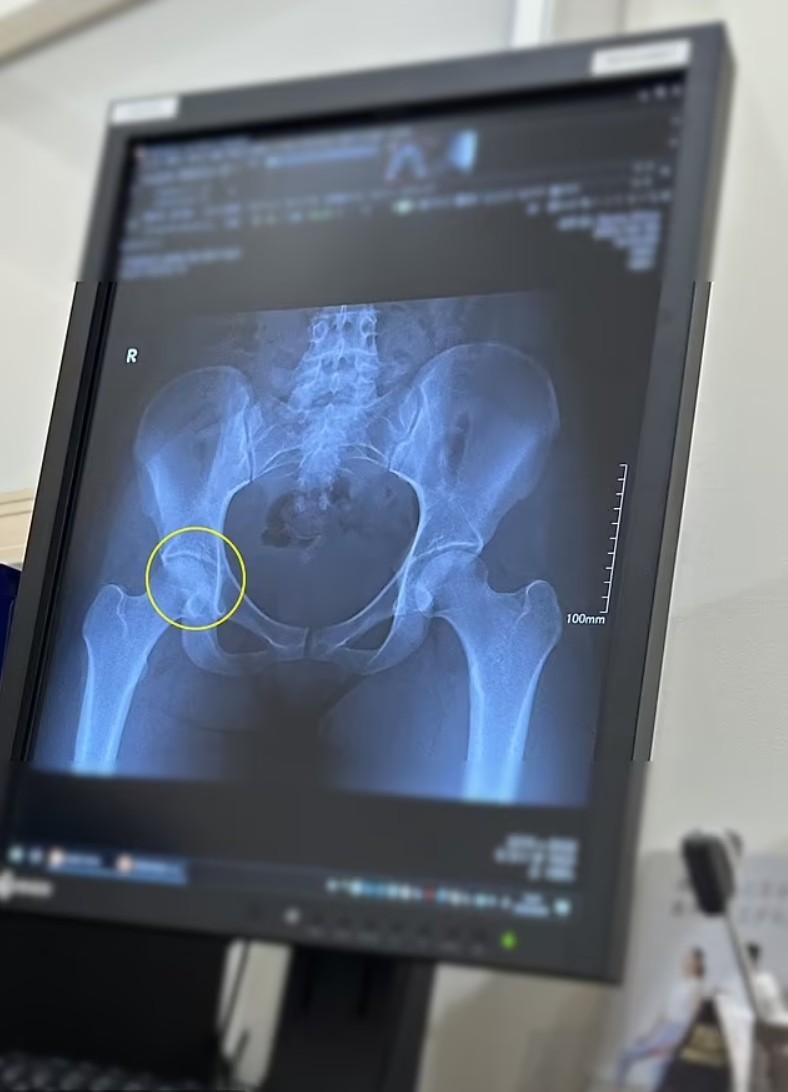

医生让她做了一系列检查,终于发现了病因——她已经骨折很长时间了。

由于长时间以不正确的姿势举起重物,她的髋部出现了应力性骨折,股骨头和髋关节周围出现了许多细小的裂缝。

这还没完,她髋骨和股骨之间的空间缩小了很多,以至于骨头一直在互相摩擦,怪不得那么疼…….

(骨折区域)